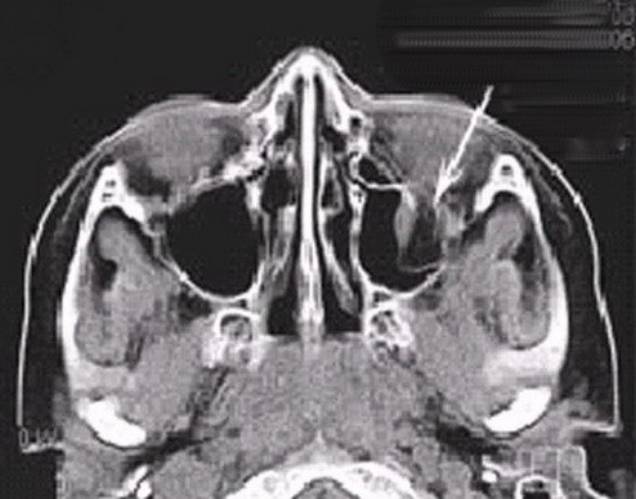

Фолликулярная киста медленно растет в течение

многих месяцев и даже лет, не вызывая никаких неприятных ощущений. Поэтому

хроническое воспаление кисты имеет бессимптомное течение. Обычно кисту

обнаруживают на рентгеновском снимке случайно. Чаще ее диагностируют при

нагноении содержимого, когда возникает одонтогенный гайморит. На рентгеновском

снимке киста представляет собой округлое образование с четкими границами.